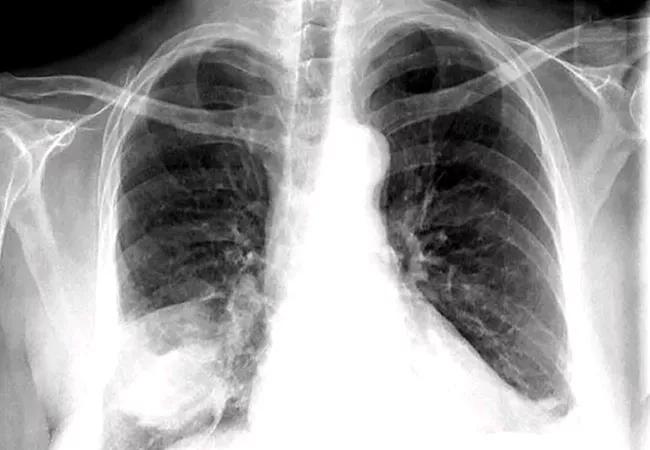

Making a diagnosis with radiographic and laboratory methods

After the level of care has been determined, radiographic and laboratory methods can be used to verify the suspected diagnosis of CAP and help convey the pathogen responsible for the infection. Chest radiographs with demonstrable infiltrates are required to diagnose CAP and to distinguish it from upper respiratory tract infection.4 Drs. Modi and Kovacs note that characteristic patterns of infiltrates may manifest within 12 hours of symptom onset. These may include:

• Focal nonsegmental or lobar infiltrates

• Multifocal bronchopneumonia or lobar infiltrates

• Focal or diffuse “interstitial” infiltrates

Keep in mind that chest radiograph reports are subject to some variability based on the interpreter. Some studies cite 65% accuracy in diagnosing viral pneumonia and 67% accuracy in diagnosing bacterial pneumonia, while others report no significant reliability in distinguishing between bacterial and nonbacterial pneumonias.5 Patients should also be screened for risk linked to occupational, travel, or endemic exposure, which can help to inform microbiologic testing and antibiotic selection.